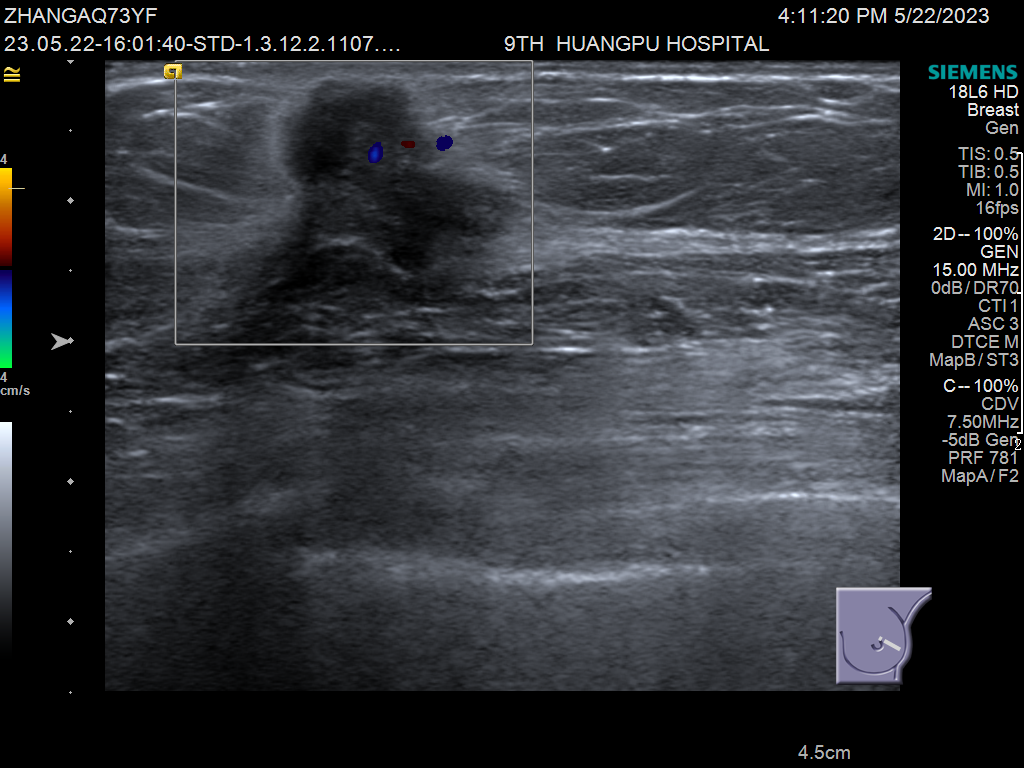

此病例为多病灶的浸润性乳腺癌患者,在手持式超声扫查时发现左乳头上方及外上方近乳腺边缘的两个病灶,术前磁共振检查发现三个病灶,再行ABVS检查,发现中间还有一个小子灶。入我院手术,病理证实小子灶为浸润性乳腺癌。

手持式超声扫查